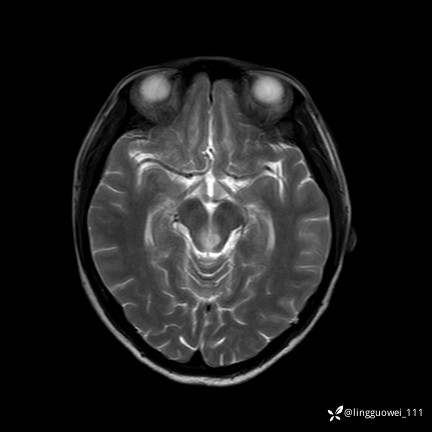

T2

img